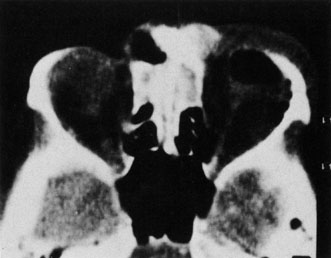

A subperiosteal abscess may rupture or invade the periorbit, resulting in an orbital abscess. This may or may not be contiguous with the subperiosteal collection on CT. There may be gas or air–fluid levels within the mass.51,56,58,59 An orbital abscess may present as an enhancing ringlike peripheral mass that can be either heterogeneous or homogeneous (Fig. 18).

Fig. 18. Orbital abscess. A. Computed tomography of an orbital abscess presenting as an enhancing intraconal mass on right side. B. T1-weighted image. C. T2-weighted image. Note area of high signal corresponding to abscess.